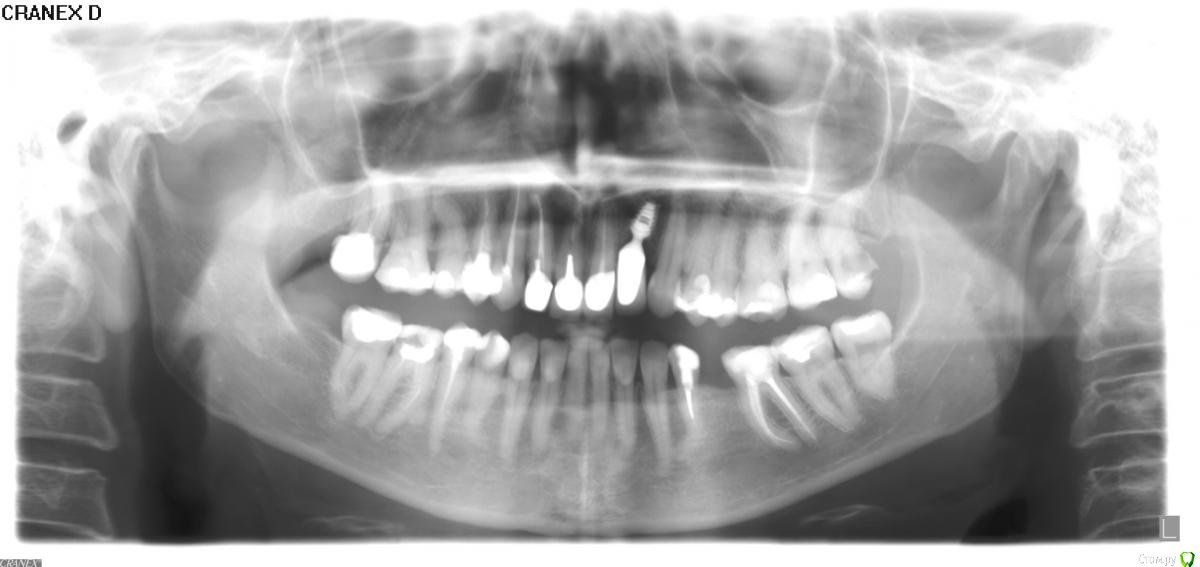

Bier Опубликовано 2 октября, 2017 Поделиться Опубликовано 2 октября, 2017 Добрый день, уважаемые доктора. В связи с тем, что у меня стоят большие пломбы ортопеды настаивают на удалении нервов и установке коронок практически на всех зубах кроме нижних передних. Подскажите, пожалуйста, действительно ли необходимы коронки на всех жевательных зубах и удаление всех нервов? нервы конечно же не удалять. Протезировать безметалловыми накладками. Но у вас куча зубов, где нервы уже удалены и не мешало бы перелечить каналы. 28зуб - удалить. Ссылка на комментарий